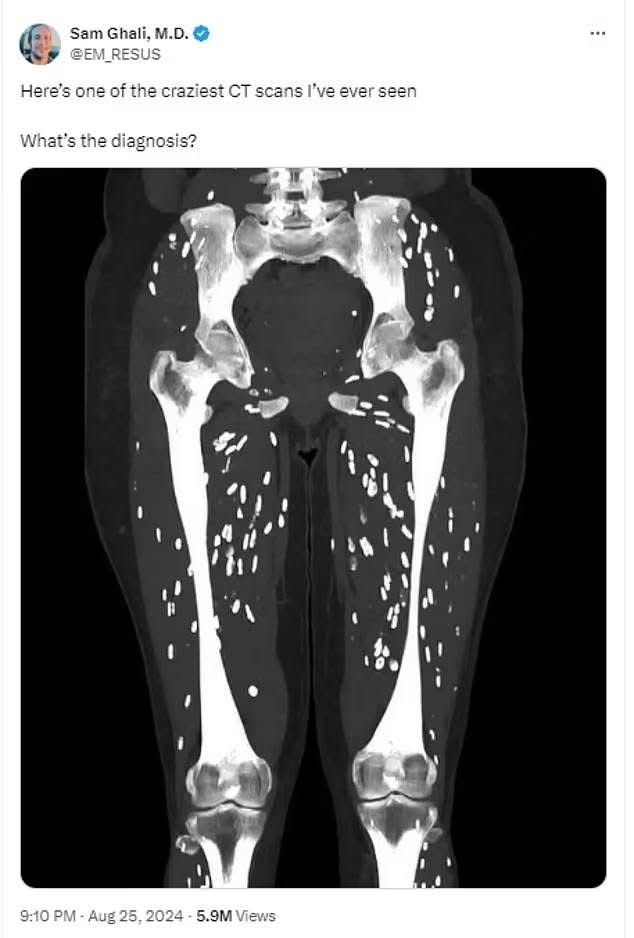

Dr Sam Ghali, një mjek i kujdesit urgjent nga Universiteti i Floridës , shkroi në mediat sociale për të ndarë një imazh të një pacienti me shenja treguese të një infeksioni parazitar të quajtur cisticerkozë dhe demete e konsumimit te mishit te derrit.

Cisticerkoza ndodh kur larvat e një lloji të krimbit të shiritit hyjnë në inde si muskuli apo edhe truri.

Ata formojnë një kist të fortë të kalcifikuar që mund të ndihet si gunga nën lëkurë dhe ndizet si nyje të bardha ovale ‘kokrra orizi’ në skanimet mjekësore.